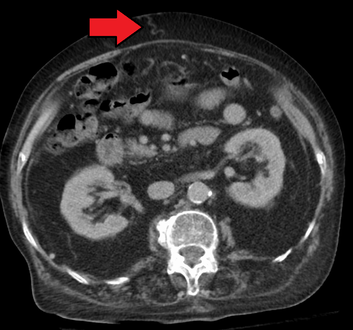

In addition, a widened (dilated) portal vein as seen on a CT scan or MRI may raise the suspicion about portal hypertension. A cutoff value of 13 mm is widely used in this regard, but the diameter is often larger than this is in normal individuals as well.[7]

A dilated portal vein (diameter of greater than 13 or 15 mm) is a sign of portal hypertension, with a sensitivity estimated at 12.5% or 40%.[13] On Doppler ultrasonography, a slow velocity of <16 cm/s in addition to dilatation in the main portal vein are diagnostic of portal hypertension.[14] Other signs of portal hypertension on ultrasound include a portal flow mean velocity of less than 12 cm/s, porto–systemic collateral veins (patent paraumbilical vein, spleno–renal collaterals and dilated left and short gastric veins), splenomegaly and signs of cirrhosis (including nodularity of the liver surface).[12]